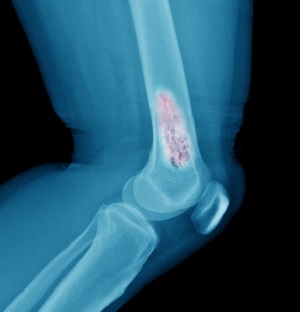

- Лучевая терапия. Облучению чаще всего подвергаются опухолевые очаги, обнаруживаемые во внутренних органах, и костные метастазы. Воздействие ионизирующим излучением помогает добиваться эффективного разрушения раковых клеток и значительного уменьшения размеров новообразований. Благодаря тому, что в израильских больницах при этом используются линейные ускорители нового поколения, негативное влияние радиации на организм сведено к минимуму и осложнений после курсов радиотерапии у пациентов не возникает.

- Рентгенография и другие.